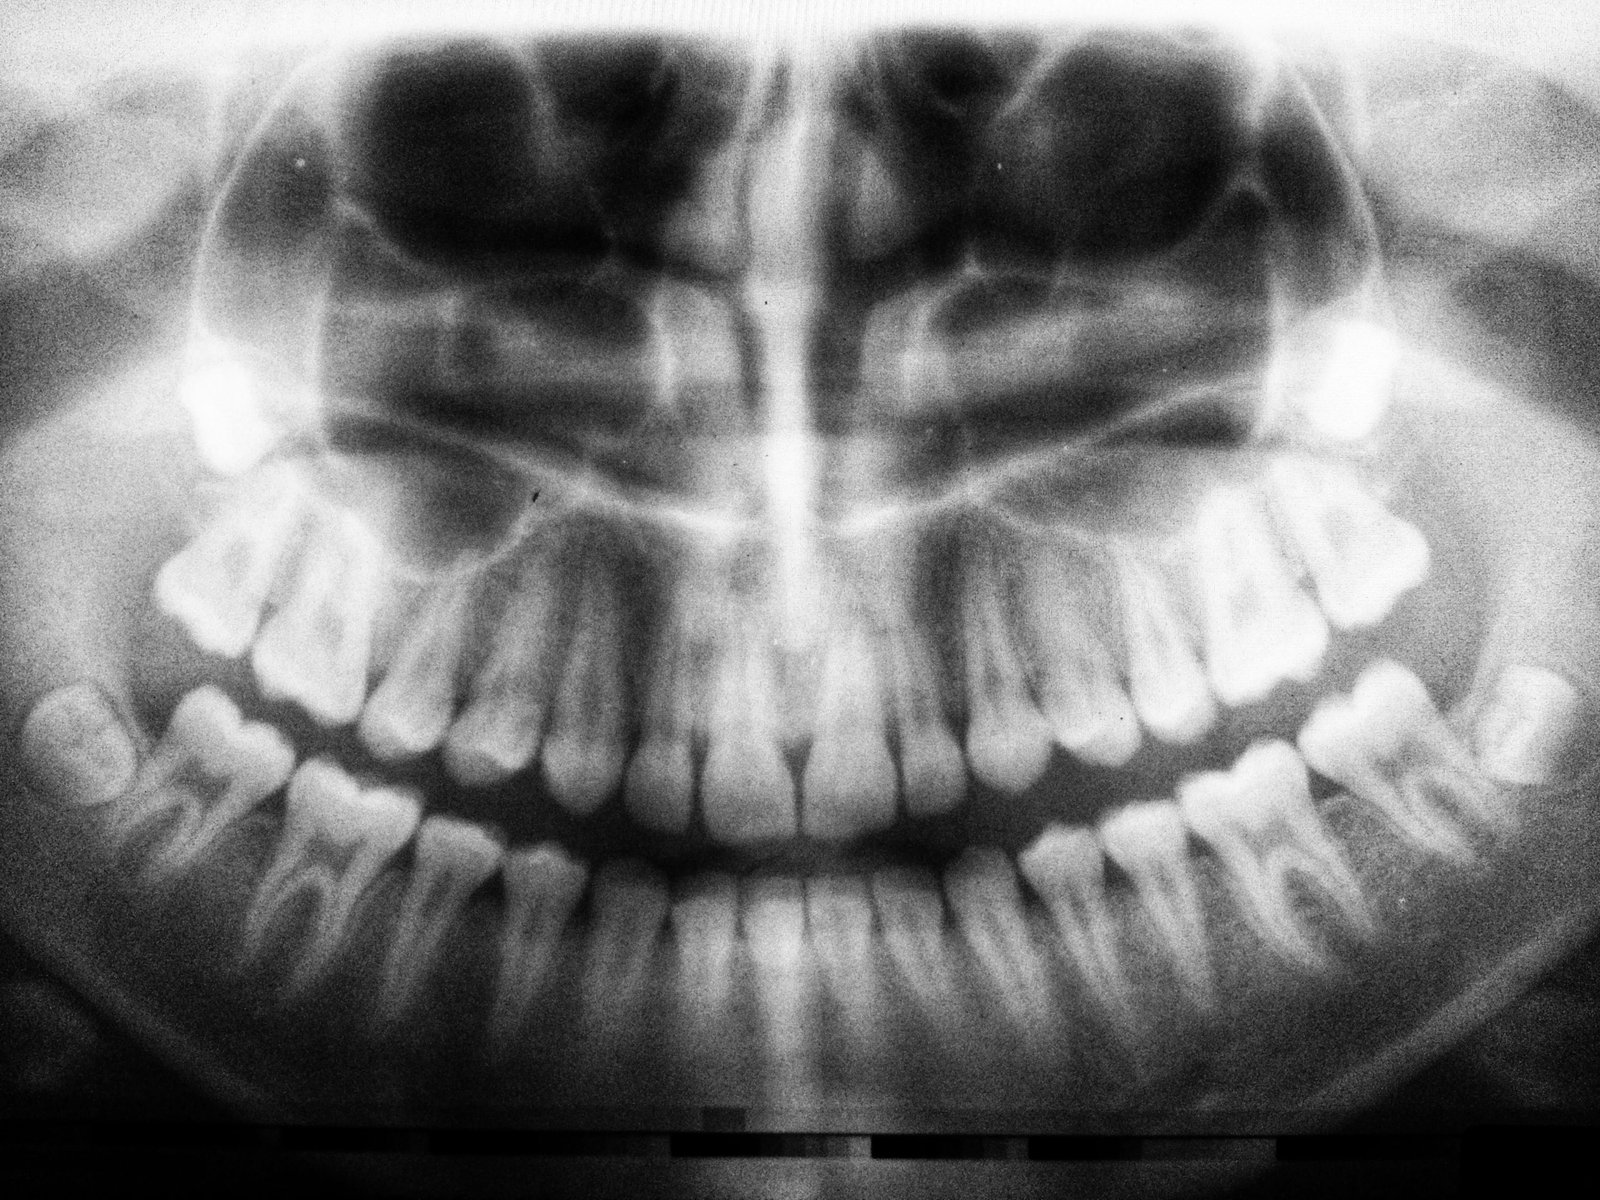

Multimodal data fusion technology integrates multiple diagnostic imaging and data sources to overcome limitations inherent in single-modality approaches within orthodontic practice. This technological framework enables clinicians to synthesize comprehensive diagnostic information and support collaborative interdisciplinary care delivery across orthodontics, oral surgery, prosthodontics, and related specialties.

Multimodal data fusion provides clinicians with more comprehensive and accurate diagnostic information compared to single-modal imaging alone. The technology facilitates dynamic monitoring of orthodontic treatment progression and enables precise evaluation of clinical outcomes. A standardized data platform derived from this approach promotes seamless integration and information exchange among orthodontists, oral surgeons, prosthodontists, and other specialists involved in oral healthcare delivery.